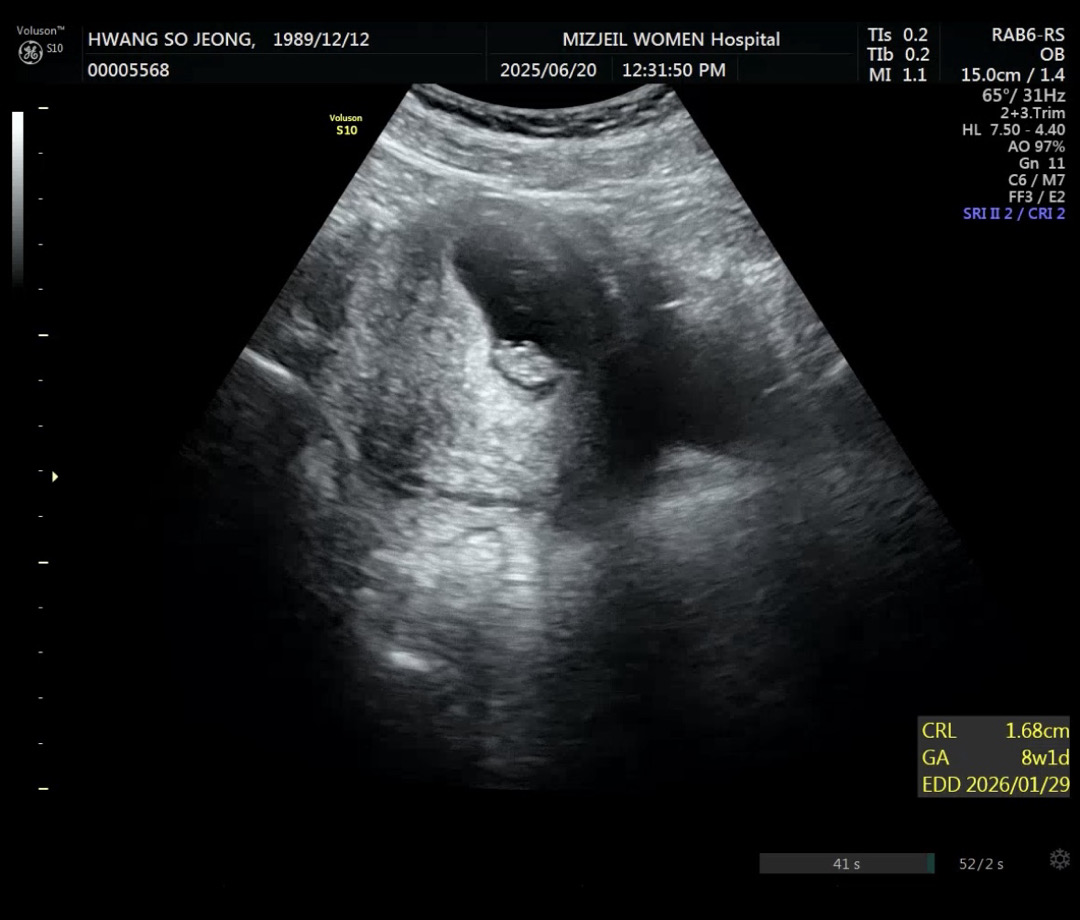

8주1일 초음파 보고왔어용

8주1일차 초음파에요 아직 뭐가뭔지 하나두 모르겠어요 또 저는 벌써부터 살이 엄청 쩠는데🫢🫣 다른 산모분들중에서도 그러신분 있나요?🧐